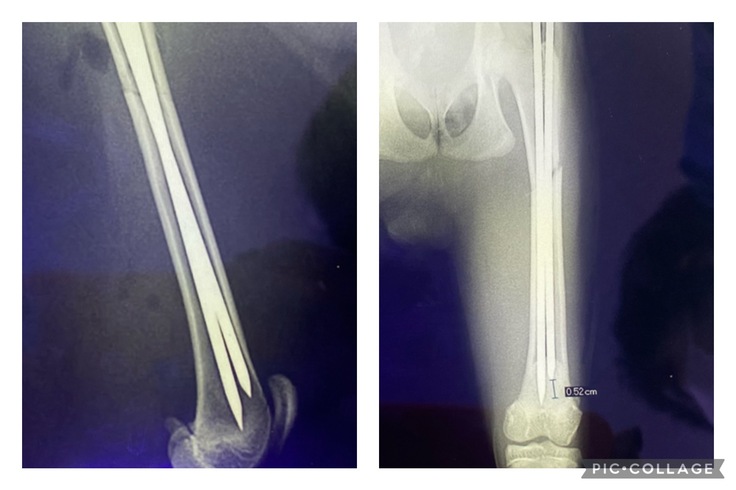

▲レントゲン写真

左大腿部の骨がポッキリ折れているのがわかります。

骨が入れ違っているのは、筋肉が収縮したためとのこと。

▲ワイヤーを抜く前に撮ったレントゲン写真

骨折した部位から骨が縦に割れてしまっています。

完治しても、骨折した足は右足よりも2割ほど短くなってしまうそうです。